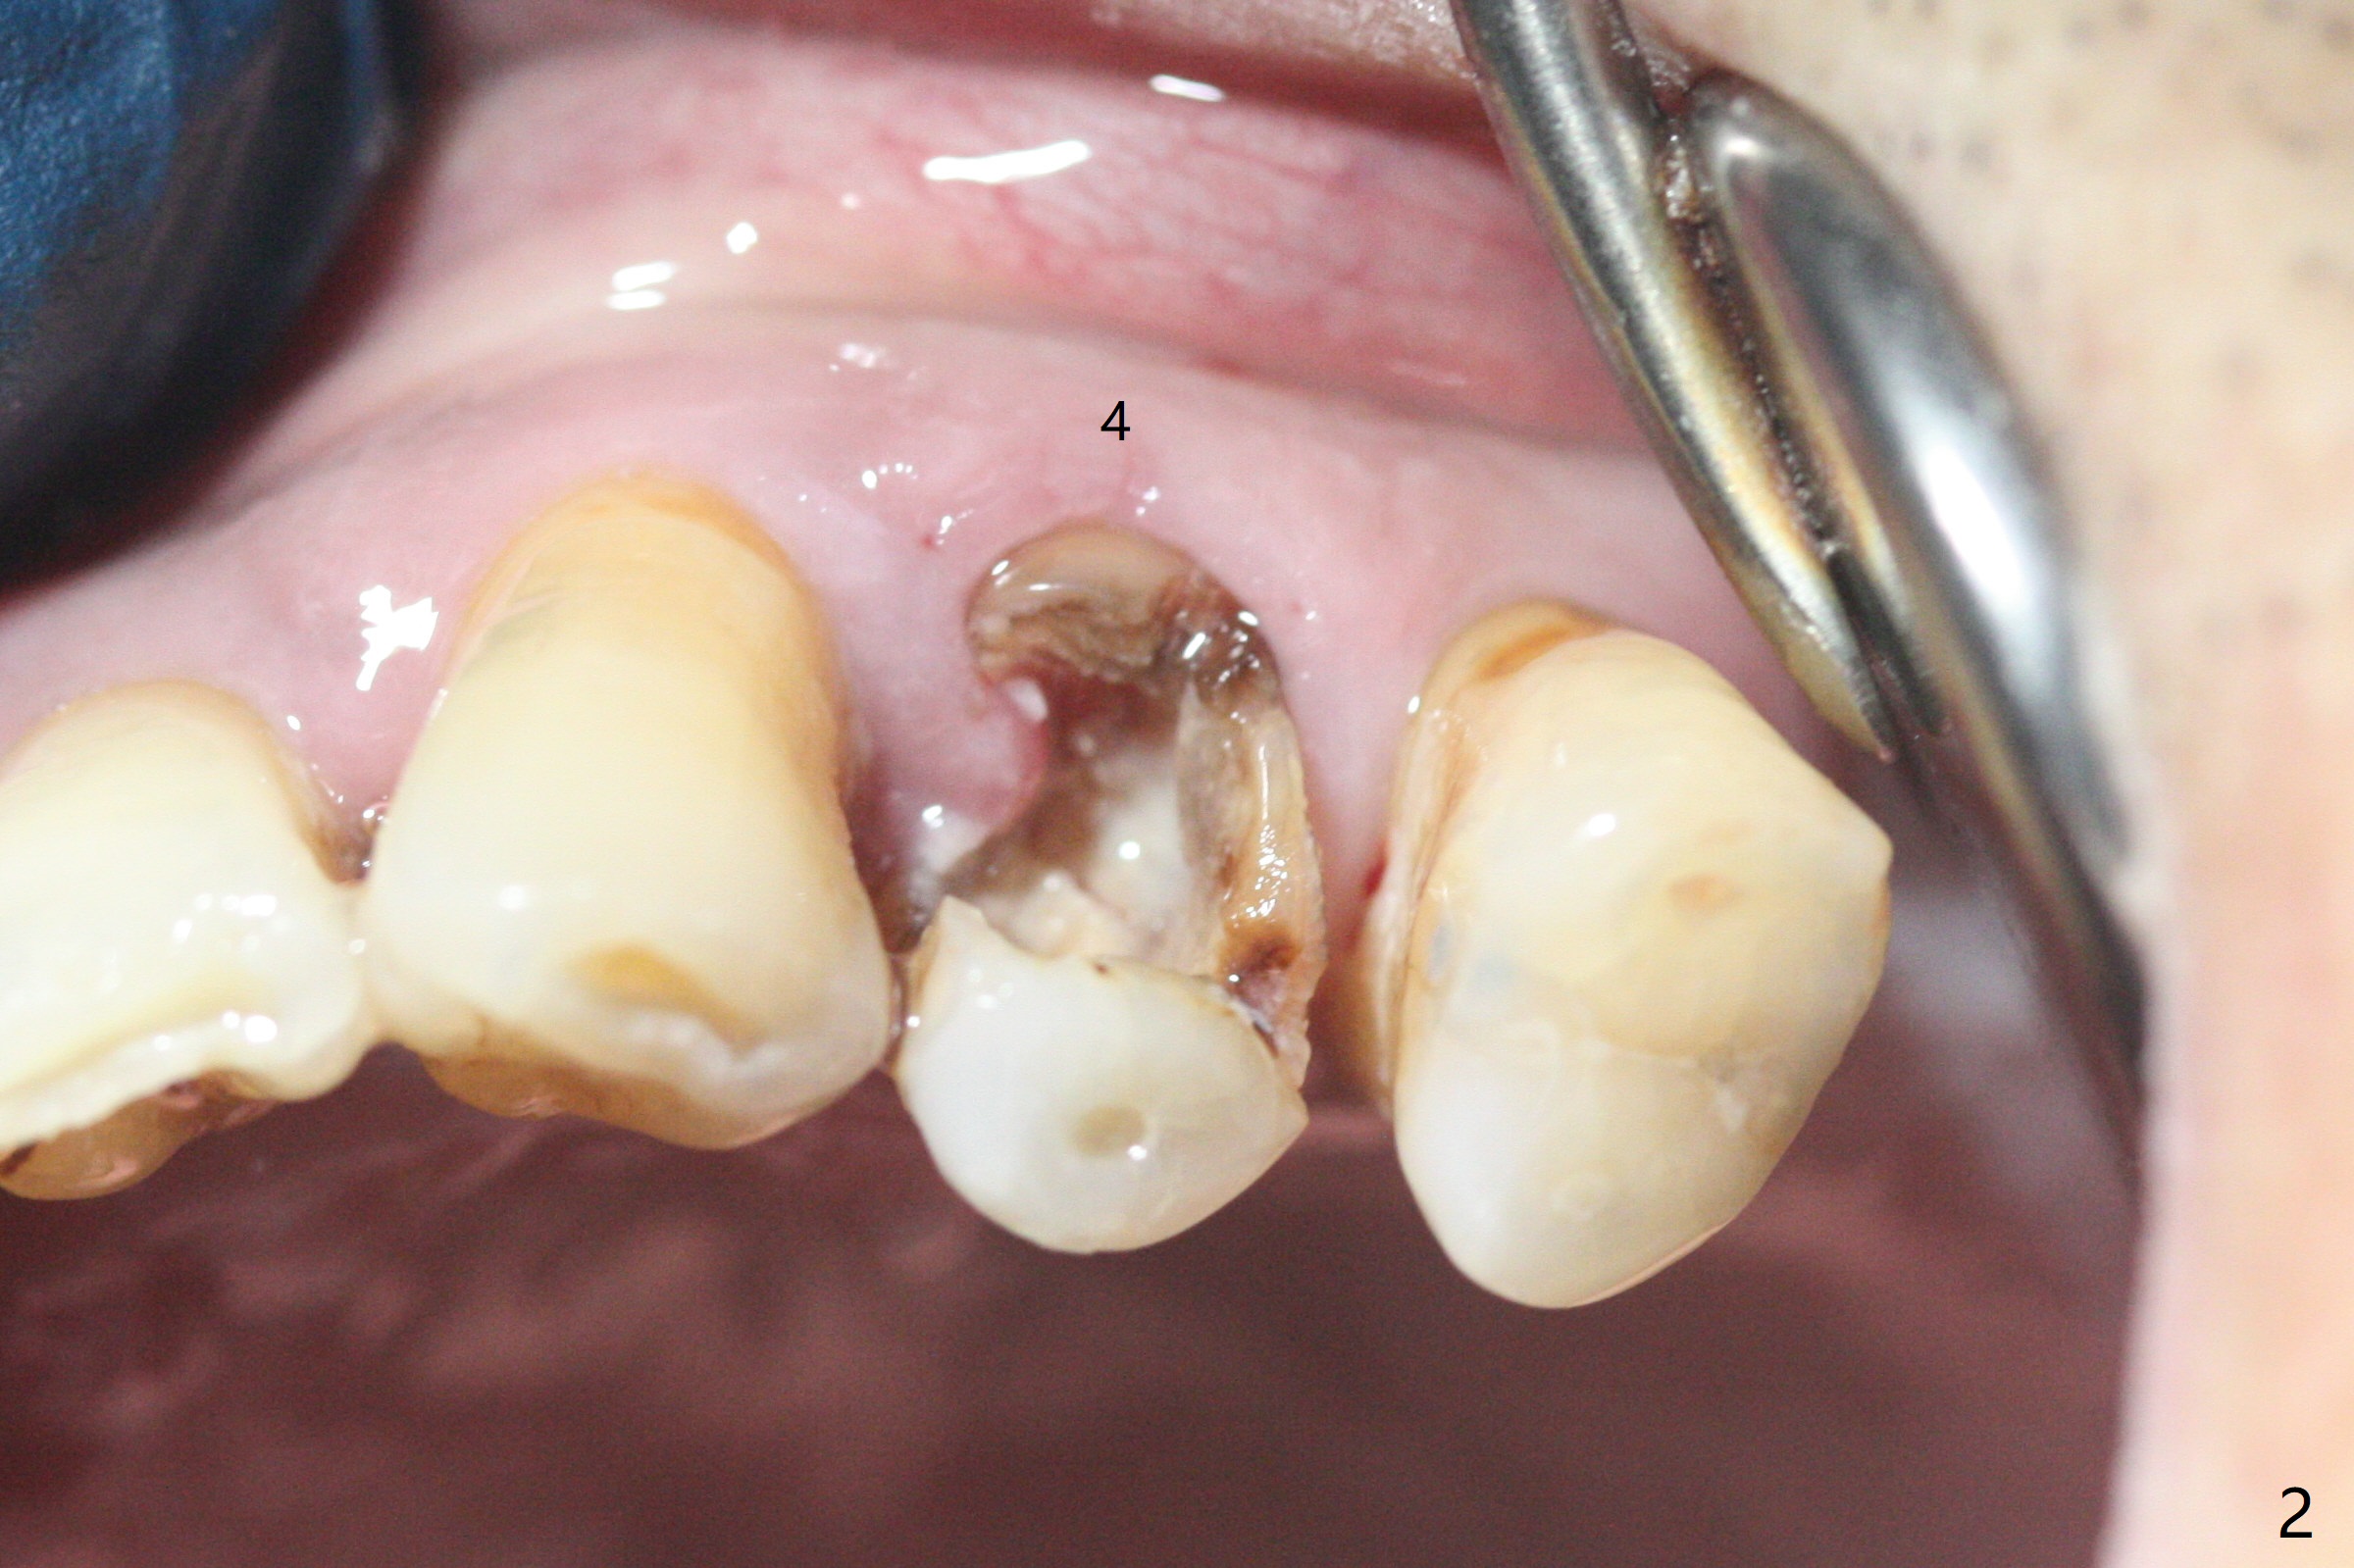

58岁男,吸烟,要求拔除断裂左上4(图一,二),邻牙(5)骨质吸收严重(图一,四),右上4,5拔除后骨质吸收(图一),所以左上4拔除(图三)位点保留(图四:人工骨,图五:GEM Cap)重要,尽管他准备做假牙。